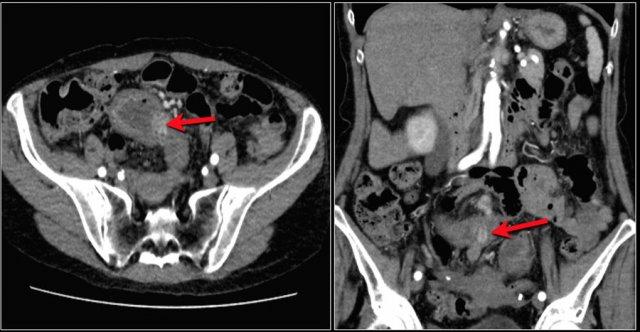

Đây là hình ảnh điển hình của u carcinoid biểu hiện là một khối mạc treo lớn với phản ứng xơ hóa desmoplastic và co kéo các quai ruột non lân cận kèm dày thành ruột (các mũi tên).

Các hình ảnh cho thấy u carcinoid biểu hiện là một khối tăng sinh mạch (mũi tên đỏ) với phản ứng xơ hóa desmoplastic (mũi tên vàng).

U carcinoid có thể gây ra phản ứng xơ hóa desmoplastic mạnh với co kéo các quai ruột và xơ hóa, đôi khi dẫn đến thiếu máu ruột.

Khối nhỏ trong lòng hồi tràng (mũi tên vàng). U carcinoid ruột non kèm theo khối mạc treo dạng tua gai với phản ứng xơ hóa desmoplastic lân cận.